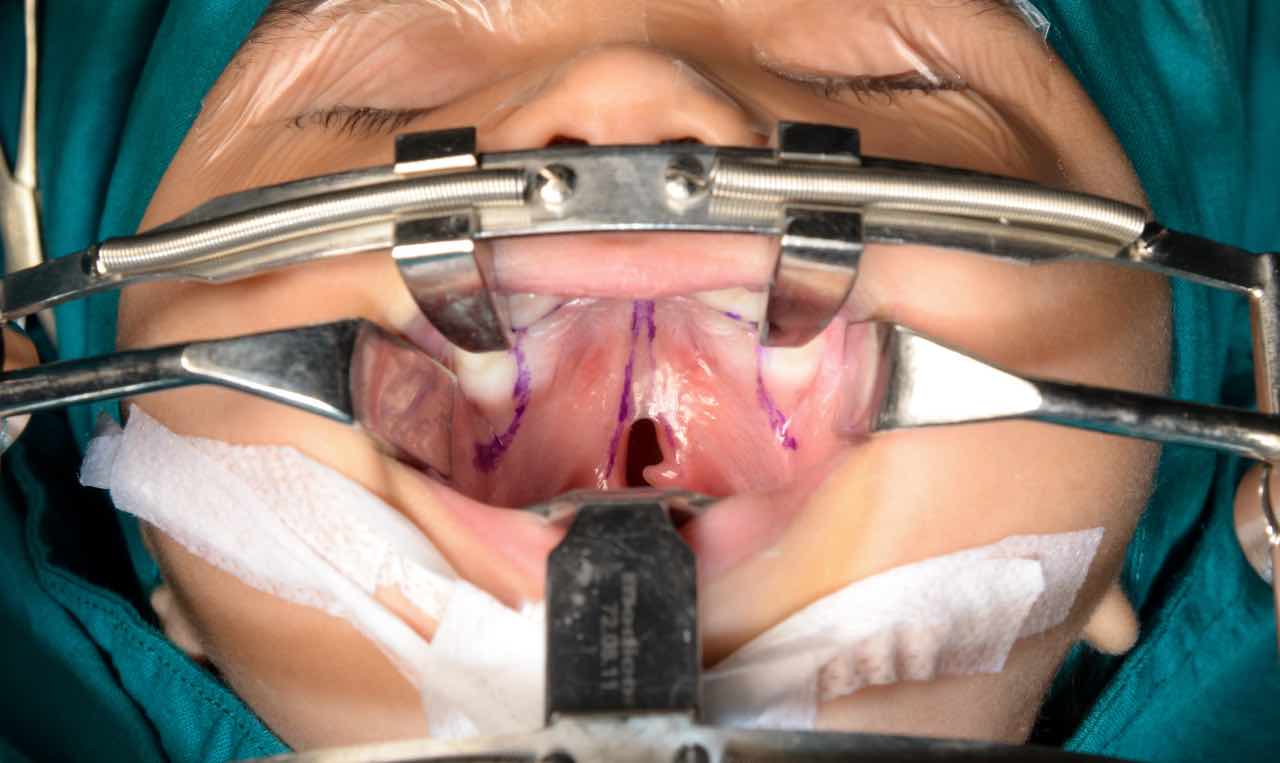

Una di queste malattie è la palatoschisi congenita, si tratta di una spaccatura, o separazione, nella faccia e nella bocca di un bambino che si verifica durante la gravidanza. La palatoschisi è il quarto difetto congenito più comune, tanto che colpisce un bambino su settecento. Andiamo a vedere le cause e le cure.

Una palatoschisi congenita è una malformazione del viso e della bocca che si verificano molto presto durante la gravidanza. Si verifica quando i tessuti non si uniscono correttamente. Può coinvolgere il palato duro (la parte anteriore ossea del tetto della bocca) e/o il palato molle (la parte posteriore morbida del tetto della bocca).

In merito alla cura della patologia, questa avviene tramite un intervento chirurgico. In genere l’operazione viene eseguita nel primo anno di vita del bambino, così da ottenere dei migliori risultati nell’arco del tempo e non andare incontro alle varie problematiche. L’intervento può essere eseguito dal sesto mese dalla nascita.